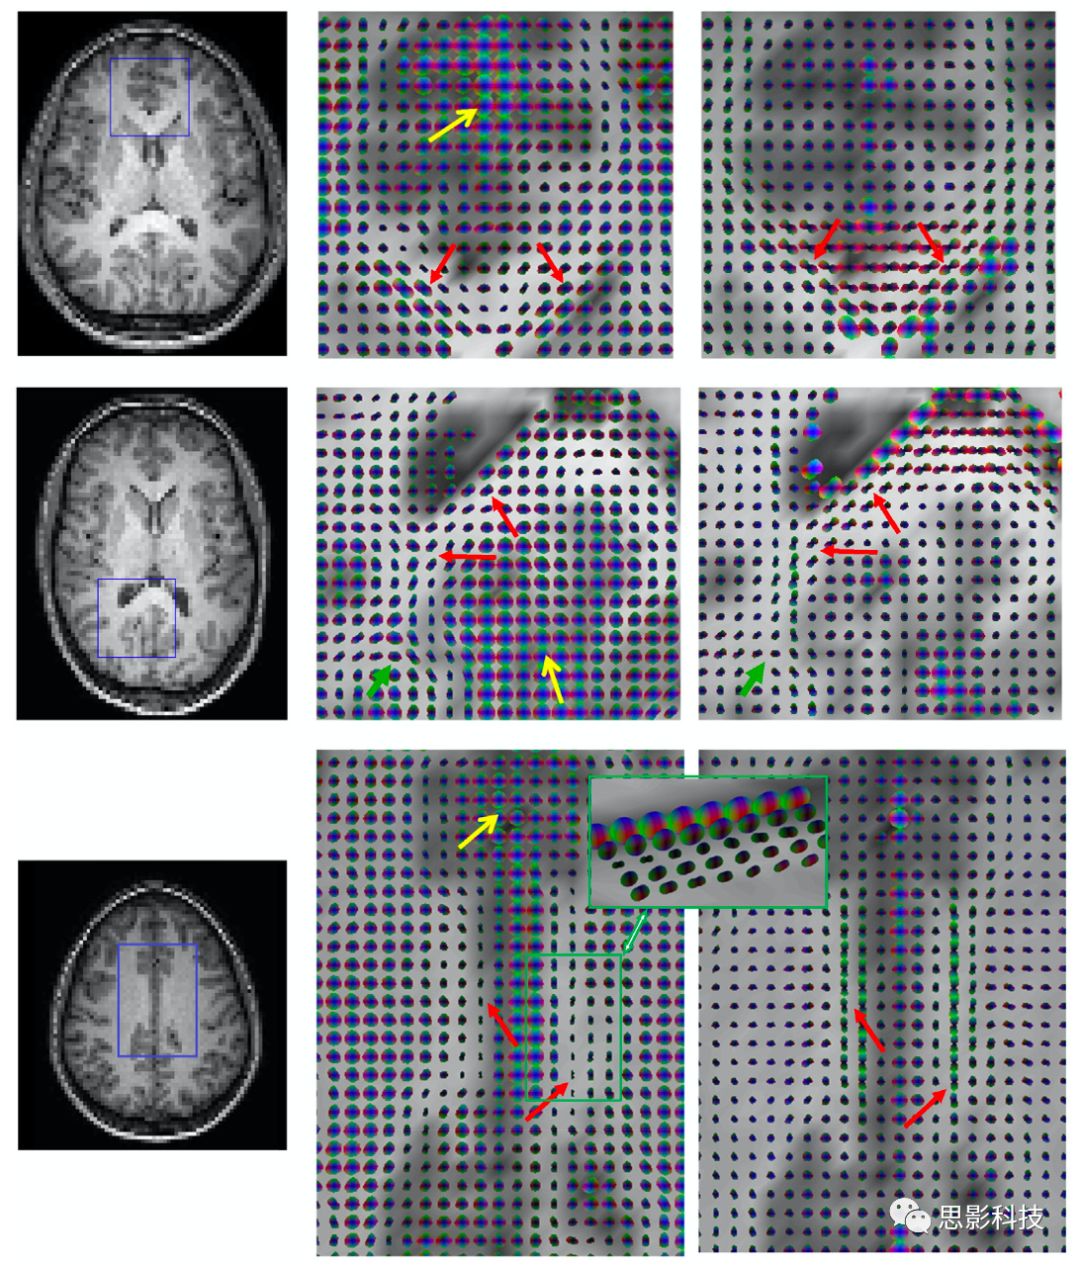

Ding等人還計算了相鄰WM體素之間信號的相關性,發(fā)現(xiàn)它們是具有可測量的各向異性特征。對于3×3×3體積中心的體素,有26個最近的鄰居,因此在靜止狀態(tài)下有26個方向的相關系數(shù)。WM中的這些值是不相等的,但它們可能適合當做是3×3張量,就如DTI中不同的梯度方向。靜息態(tài)下BOLD信號的函數(shù)相關張量(FCT)可用類似于DTI張量的方式處理。例如,使用它們的主特征值定義主方向,而類似的各向異性分數(shù)(FA)就很容易得到。Wang等人觀察到,感覺運動系統(tǒng)中沿WM纖維束的靜息態(tài)相關性的平均FA與卒中患者的臨床評分顯著相關。而Chen等人將FCT擴展為動態(tài)FCTdFCT)。其衍生出來的定量指標,即動態(tài)FA,被證明是可有效的識別輕度認知障礙(MCI)。一般來說,FCT定義的纖維束遵循DTI定義的纖維束。5顯示了單個腦切片的DTIFCT之間的比較比較結果,而圖6顯示了胼胝體和扣帶回中的單個體素的定向橢球體。盡管FCTs似乎與DTI數(shù)據(jù)一致,但它們也有一些局限性。僅使用最近鄰體素,使得FCTs對噪聲很敏感。此外,相鄰的體素比對角的體素具有更高的相關性,從而導致了方向的偏差。

5. 第一行是在沒有任何擴散加權的情況下獲得的,只使用了在四個不同TEs的靜息態(tài)波動-泛函相關張量中的相關性。下面一行顯示了由M0R2*圖像、擴散張量和FA映射構造的功能相關張量。

Fig 6  胼胝體的膝部和壓部以及扣帶回中的時間功能相關性張量(FCT)和擴散張量。左圖為T1,左列的方框區(qū)域中的FCT和同一區(qū)域中的擴散張量。 FCT形成的通路與擴散張量(紅色箭頭)顯示的通路基本一致。